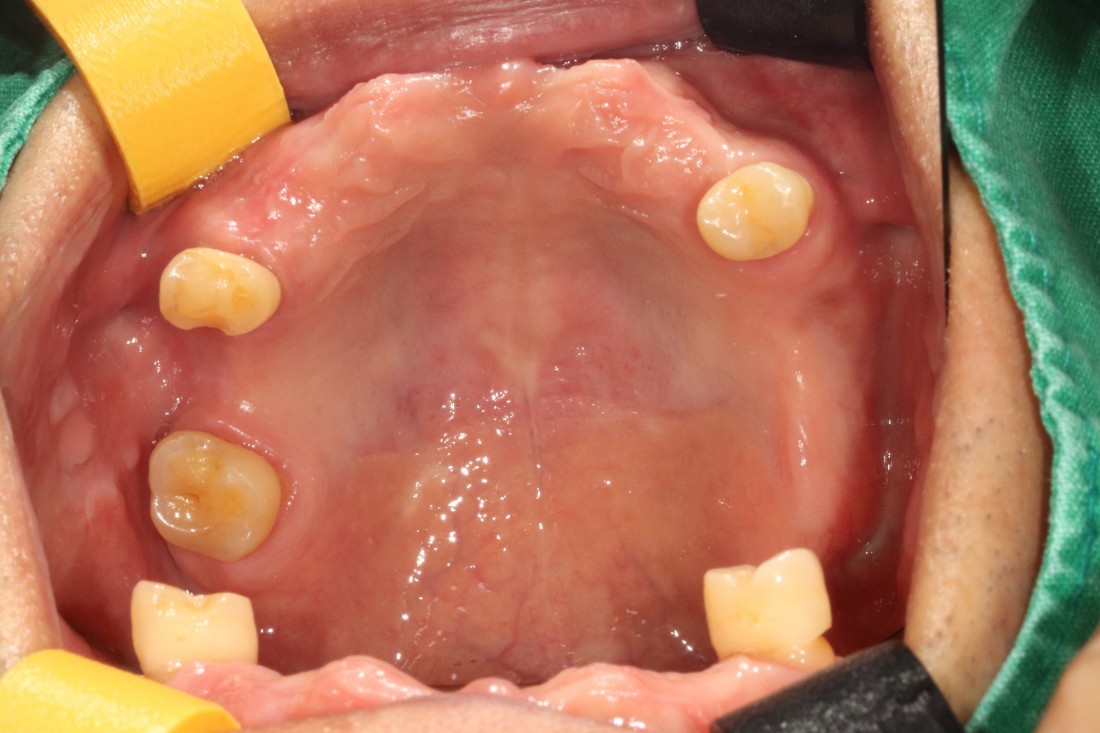

전남광주 임플란트 치과에서는

디지털가이드 임플란트 수술방법으로

한 번에 8개 이상의 임플란트를

심을 수 있습니다.

위, 아래 전체 임플란트를

단 두 번의 수술만으로 완성할 수 있어

임플란트 치과에 자주 내원하지 않으셔도 되고,

붓기 / 출혈 / 통증도 적기 때문에

빠른 회복을 기대할 수 있습니다.